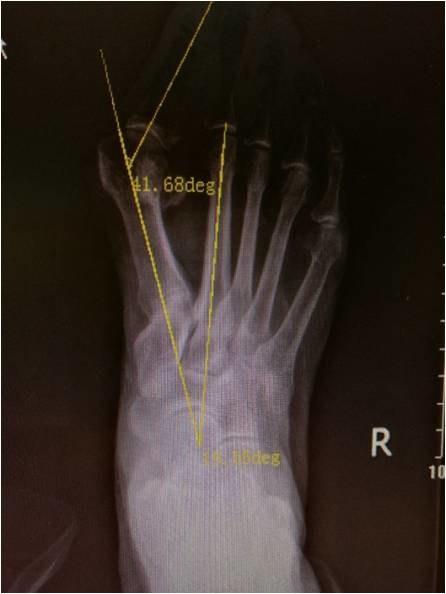

5、X线摄片:距骨与第一跖骨纵轴线交叉成角大于15°,跟骨跖面和距骨纵轴线夹角小于30°。